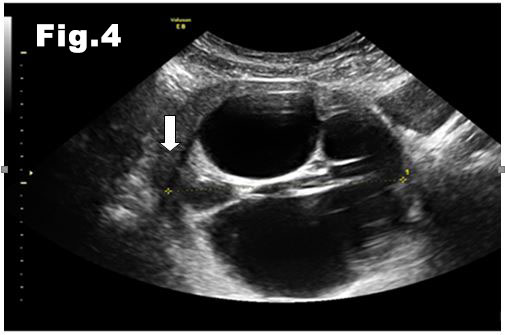

On transvaginal scan, an enlarged multilocular cyst was noted. The cyst was confined to the uterus and the endometrial cavity could be clearly seen on its entire length (fig. 1). The endometrium was thin as the patient was still under the influence of Progesterone.

![Cystic fibroids</br> [Feb 2017]](http://s834315022.websitehome.co.uk/wp-content/uploads/2020/11/cotm-feb2017-fig1.jpg)